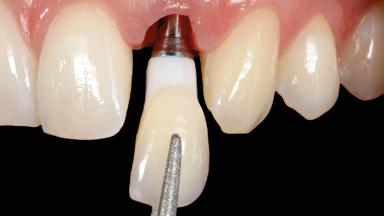

Immediate Implant Placement and Immediate Provisionalization with a Prefabricated-Shell Provisional Crown

In this case, Arndt Happe describes how he achieved a stable outcome at 5 years by giving careful attention to the coronal aspect of the transmucosal area of the provisional, creating a slim emergence profile.

Loading Protocol Immediate

Implant-supported provisional restoration Required, elevated esthetic and/or functional demands